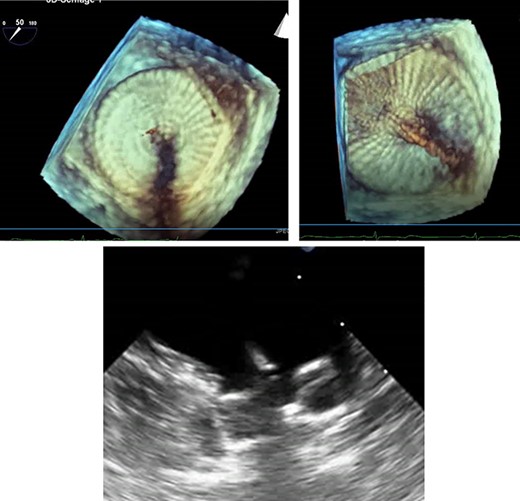

A treatment review for AF was undertaken, but no further action such as MAZE, pulmonary vein isolation, electrophysiology intervention or rhythm control were considered viable strategies. An LAA occluder implantation (Amplatzer Amulet LAA Occluder, Abbott) was carried out under transoesophageal echocardiography (TEE)-guidance and general anaesthesia (Figs 1 and 2). The left atrium was accessed via the right femoral vein (7F 8.5F catheter). The transseptal puncture with an SL1 catheter was pressure-controlled and TEE-guided posterior–inferior, straight to the optimal position. A 6F pigtail catheter was inserted for LAA angiography in right anterior oblique 30°, cranial 20° and caudal 0°.

TEE for interventional LAA occluder implantation; TEE controlled, unsuccessful LAA occluder implantation due to difficult LAA morphology.

The patient’s anatomy showed a large funnel-shaped ostium, with narrow neck and shallow depth and chicken-wing morphology with 90° anterior/frontal angulation. TEE measurements showed a landing zone diameter of ~12–13 mm. A 16 mm occluder was selected. The TorqueVue lock 12F was exchanged via a stiff wire and positioned in the left superior pulmonary vein. No satisfactory position was achieved. For the proximal part, shortly after the ostium with a maximum depth of 12 mm the occluder was too small and exchanged for a 20 mm occluder. This could not be securely positioned; the corpus dislocated in the Timed Up and Go test because of limited contact with the LAA surface. A new transseptal puncture was performed in a more posterior and superior position, the CS catheter removed, and the 7F sheath changed to the SL1. The Amplatzer Amulet 16/20/25 mm LAA occluder implantation remained challenging due to the unusual anatomy with an atypical position of the auricular appendage. Finally the procedure was aborted in favour of a LAA clip.